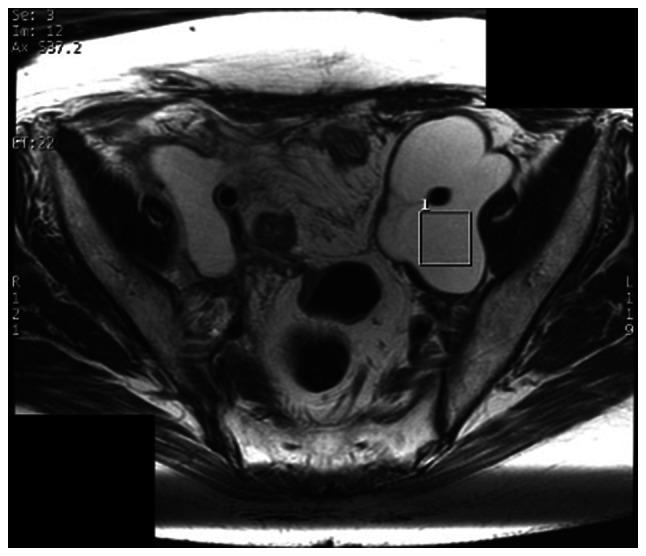

Due to the invasiveness of sample collection, treatment for an abscess in the pelvis, such as a gynecological abscess, is often started without a culture test. A test that could predict the appropriate antibiotic and clinical course without invasiveness prior to treatment initiation would be useful. Magnetic resonance spectroscopy (MRS) can be used to detect metabolites in an abscess and has the potential for evaluation of gynecological abscesses. The present study investigated the use of MRS for the evaluation of gynecological abscesses, using next-generation sequencing (NGS) for detection of true pathogenic bacteria. A total of 16 patients with a gynecological abscess who were treated at Keio University Hospital (Tokyo, Japan) from July 2015 to September 2016 and underwent MRS were recruited to the present study. If available, samples from drainage or surgery were used for detection of true pathogenic bacteria based on analyses of bacterial flora using NGS of 16S ribosomal DNA. MRS signals, NGS results and clinical course were then compared. All patients gave written informed consent after receiving an oral explanation of the study and the study was approved by the institutional research ethics committee. Of the 16 patients, six had MRS signals with a specific peak at 1.33 ppm, which suggested the presence of lipid or lactic acid. However, there was no significant association between metabolism, MRS signals, pathogenesis and clinical course. Only in cases of infectious lymphocele were there cases with a lactic acid peak that seemed to improve without drainage. In conclusion, the present study was not able to show marked usefulness of MRS for the identification of pathogenic bacteria and prediction of the clinical course; however, MRS may be useful for predicting the need for drainage in patients with infectious lymphocele. This study was registered as a clinical trial in the UMIN Clinical Trials Registry (registration no. UMIN000016705) on March 11, 2015.

由于样本采集具有侵入性,盆腔脓肿(如妇科脓肿)的治疗通常在未进行培养检测的情况下就开始了。一种能够在治疗开始前非侵入性地预测合适抗生素和临床病程的检测方法将很有用。磁共振波谱(MRS)可用于检测脓肿中的代谢物,具有评估妇科脓肿的潜力。本研究使用下一代测序(NGS)检测真正的致病细菌,探讨了MRS在评估妇科脓肿中的应用。2015年7月至2016年9月在庆应义塾大学医院(日本东京)接受治疗并接受MRS检查的16例妇科脓肿患者被纳入本研究。如果有引流或手术样本,基于对16S核糖体DNA的NGS分析细菌菌群,用于检测真正的致病细菌。然后比较MRS信号、NGS结果和临床病程。所有患者在接受研究的口头解释后均签署了书面知情同意书,该研究获得了机构研究伦理委员会的批准。16例患者中,6例MRS信号在1.33 ppm处有特定峰,提示存在脂质或乳酸。然而,代谢、MRS信号、发病机制和临床病程之间没有显著关联。仅在感染性淋巴囊肿病例中,有乳酸峰的病例似乎在未引流的情况下有所改善。总之,本研究未能显示MRS在鉴定致病细菌和预测临床病程方面有显著作用;然而,MRS可能有助于预测感染性淋巴囊肿患者是否需要引流。本研究于2015年3月11日在UMIN临床试验注册中心注册为临床试验(注册号UMIN000016705)。